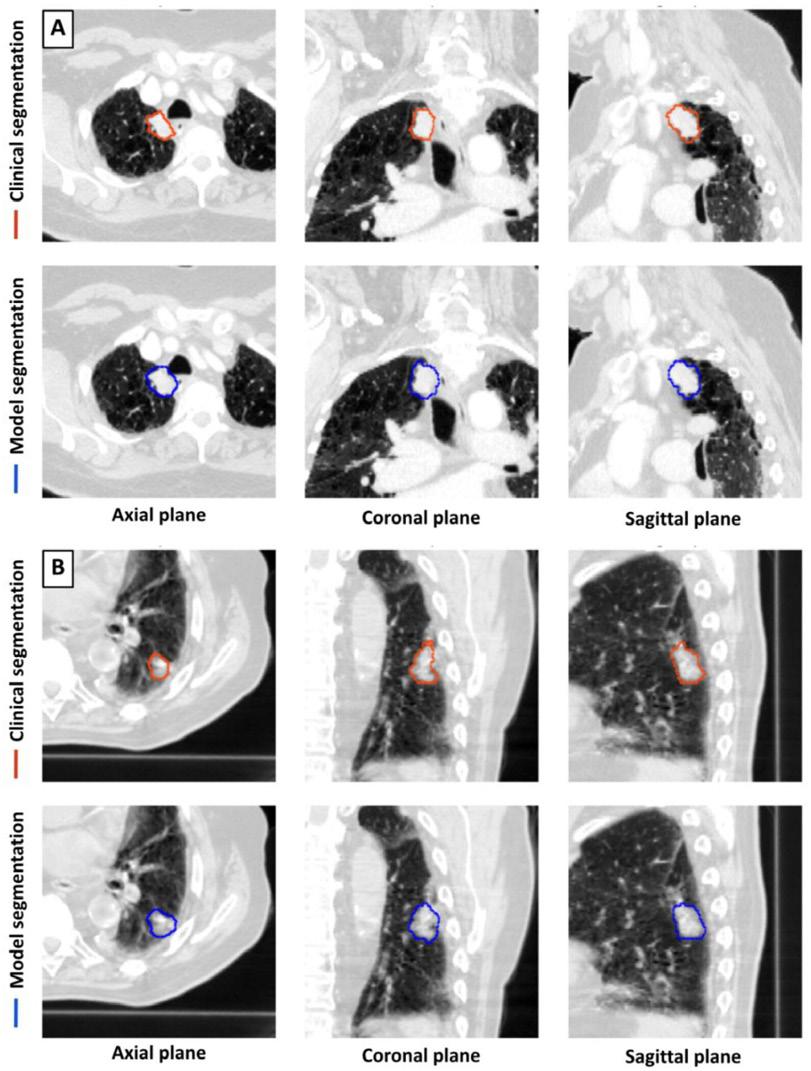

Figura 3. Ejemplos de segmentación clínica y de modelos. (A) Mujer de 71 años con cáncer de pulmón de células no pequeñas (CPCNP) del conjunto de prueba interno. (B) Hombre de 87 años con CPCNP del conjunto de prueba externo. Ambos pacientes se sometieron a radioterapia. Se muestran las exploraciones de simulación por TC adquiridas antes de la radioterapia. Las segmentaciones clínicas representan los contornos desarrollados en el proceso de planificación de la radioterapia.

con las de las tres segmentaciones de médicos para generar los valores de DSC modelo-médico para cada emparejamiento.

El modelo logró una sensibilidad del 92% (92/100) y una especificidad del 82% (41/50) en la detección de tumores pulmonares en el conjunto de prueba de exploración combinada de 150 tomografías computadas.

En un subconjunto de 100 tomografías computarizadas con un solo tumor pulmonar cada una, los DSC medianos de segmentación entre el modelo y el médico y entre el médico y el médico fueron 0,77 y 0,80, respectivamente. El tiempo de segmentación fue más corto para el modelo que para los médicos.